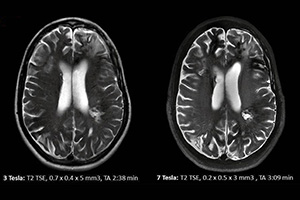

mr

Manyetik Rezonans (MR)

Manyetik Rezonans tıbbı teknolojinin önemli basamaklarından biridir. Temel çalışma prensibi...